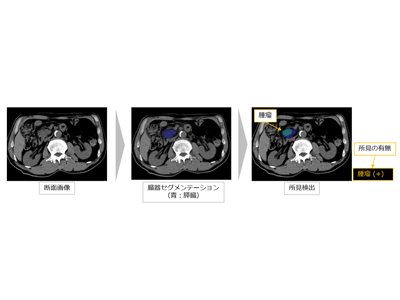

造影CT画像から膵臓がん疑い所見を検出する技術を開発していた

富士フイルム株式会社は11月1日、腹部の非造影CT画像からAI技術を活用して膵臓がんが疑われる所見の検出を支援する技術を開発し、今年4月に開発した膵臓がんの検出を支援する技術の適用対象を、造影CT画像から非造影CT画像へ拡大したと発表した。この研究は、同社と神戸大学大学院医学研究科の児玉裕三教授、村上卓道教授らの研究グループによるもの。

研究グループは、CT画像から膵臓がんの早期発見を支援するAI技術の開発を目指して2021年8月に共同研究を開始し、今年4月には、腹部の造影CT画像から膵臓がんが疑われる所見を検出する技術を開発した。

今回、約1,000症例の非造影CT画像をAIに学習させ、膵臓がんの直接所見である腫瘤、間接所見である膵萎縮・膵管拡張を検出する技術の開発に成功。造影CT画像に比べてコントラストが低く不明瞭な非造影CT画像にも対応し、膵臓がんの検出を支援する技術の適用対象を拡大させた。これにより、人間ドックなどでもこの技術が活用され、より初期の段階での膵臓がんの発見につながることが期待できる。